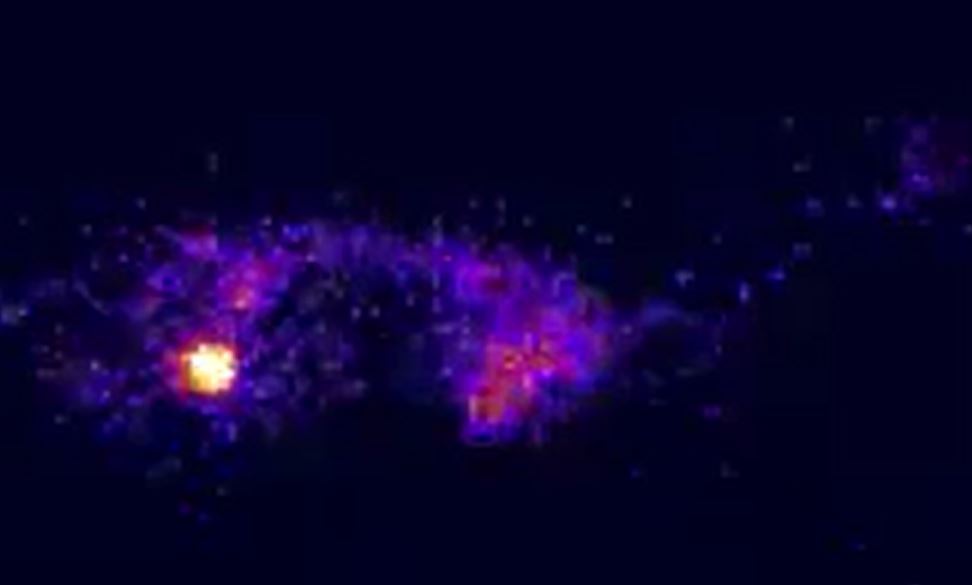

Q

Is this normal?

A

Yes.. Injection site.. splenic vein… liver and lastly heart

From left to right